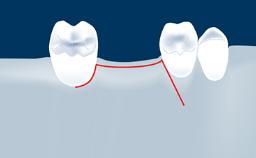

This deficit reduces the distance between the maxillary sinus floor and the alveolar process, so that reconstructing the vertical bone height by means of a sinus floor elevation procedure may be a prerequisite for placement of dental implants of the correct dimensions and in the ideal three-dimensional positions in order to achieve optimal functional and esthetic treatment outcomes while respecting relevant anatomical structures.

• list the indications for the lateral SFE technique

• describe the surgical treatment concept and steps for the lateral SFE technique and assess the prognosis of this procedure